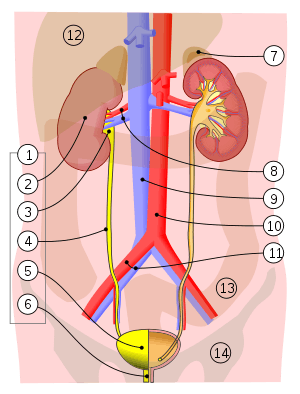

1. Human urinary system: 2. Kidney, 3. Renal pelvis, 4. Ureter, 5. Urinary bladder, 6. Urethra. (Left side with frontal section) 7. Adrenal gland Vessels: 8. Renal artery and vein, 9. Inferior vena cava, 10. Abdominal aorta, 11. Common iliac artery and vein With transparency: 12. Liver, 13. Large intestine, 14. Pelvis | |